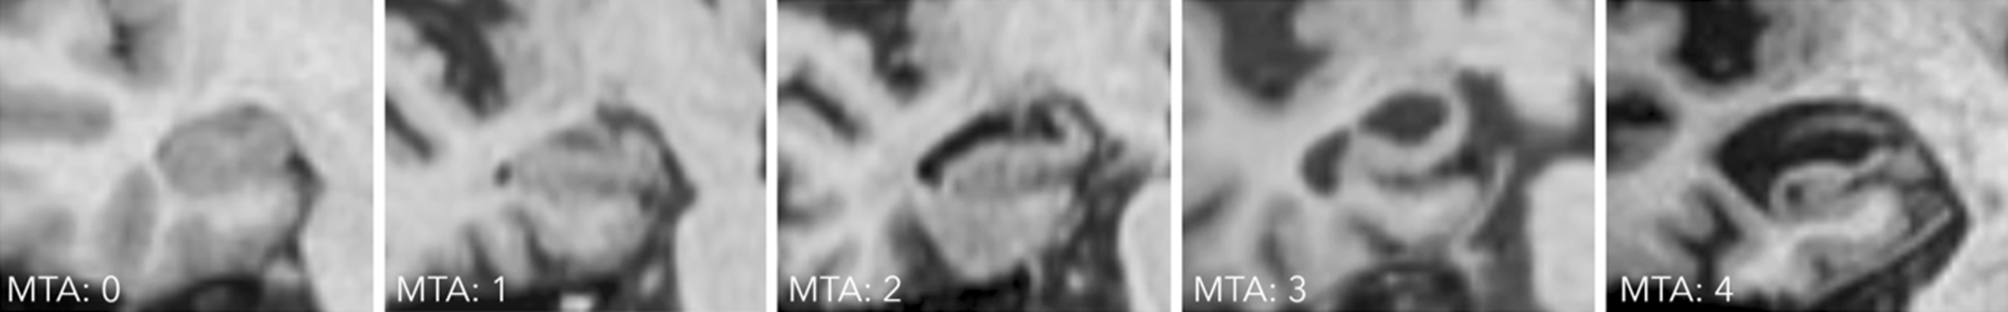

Medial temporal lobe atrophy

The degree of medial temporal lobe atrophy can be assessed using the medial temporal lobe atrophy (MTA) score assessed on coronal planes perpendicular to the long axis of the hippocampus (illustrated in Fig. 2). MTA 0 presents a normal width of the choroid fissure, the temporal horn, and a normal hippocampal volume; MTA 1 is characterized by a marginally widened choroid fissure; MTA 2 shows a moderately widened choroid fissure, a mild enlargement of the temporal horn, and a mild loss of hippocampal volume; MTA 3 is characterized by a markedly widened choroid fissure, a moderate enlargement of the temporal horn, and a moderate loss of hippocampal volume; and MTA 4 is defined as a markedly widened choroid fissure, a marked enlargement of the temporal horn, as well as a marked loss of hippocampal volume.

Fig. 2

Medial temporal atrophy scale